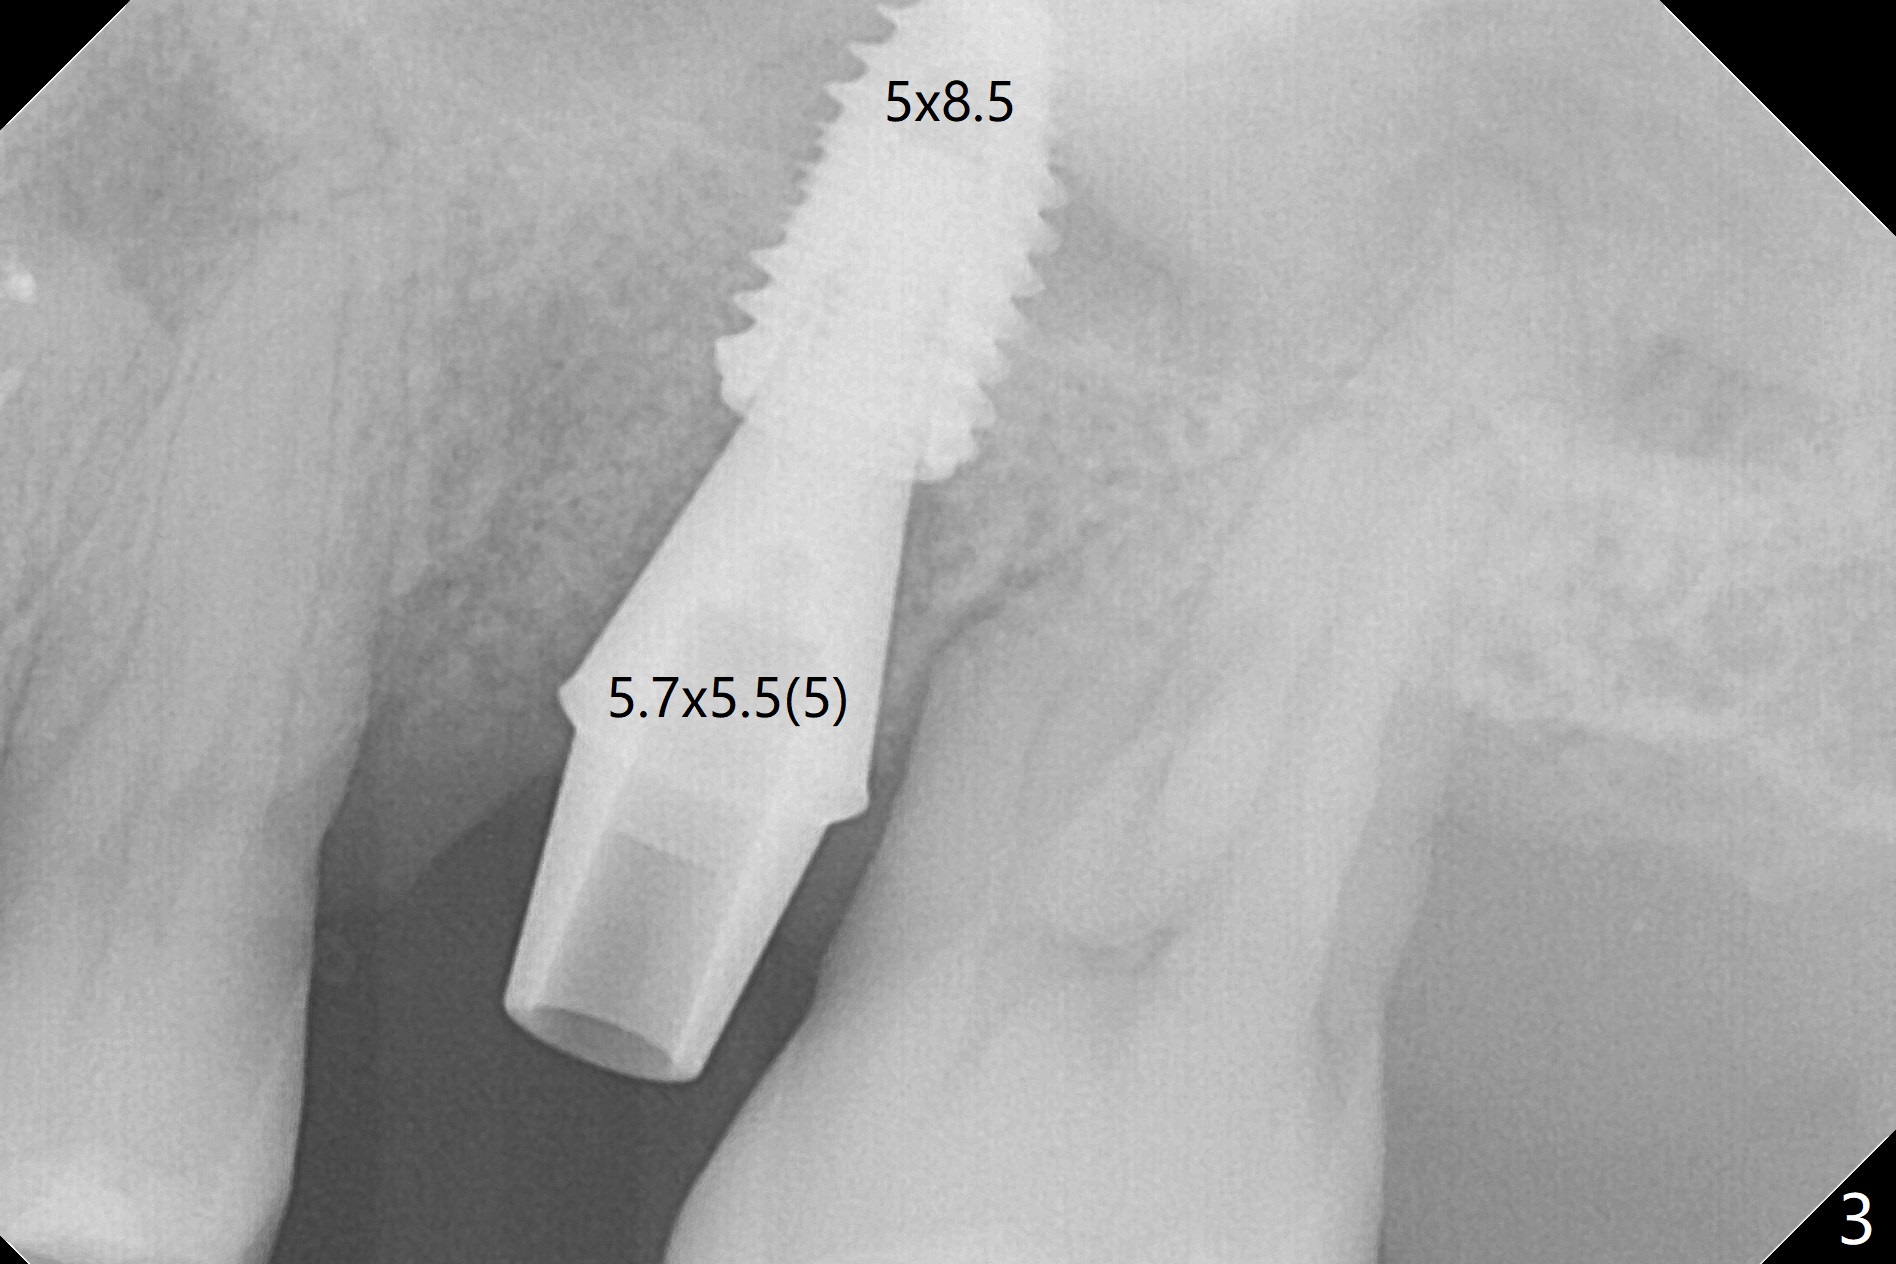

Six months post 2nd placement at #14, the 5x11 mm IBS implant is unstable. The patient smokes a cigarette a day.  After implant removal, the palatal wall of the osteotomy is intact, although low.  With removal of minimal granulation tissue, a 5x10 mm IS dummy implant is placed with stability and slightly subgingival palatal (Fig.1,2).  A 5x8.5 mm definitive implant is placed with ~ 40 Ncm and 3-4 mm subgingival palatal (Fig.3,4).  A 5.7x5.5(5) mm abutment is placed to hold periodontal dressing in place.  If the implant fails again, bone graft should be placed.  The abutment and implant are stable 4.5 months postop (Fig.5); a provisional is fabricated for progressive loading.  The provisional at #14 is narrow mesiodistally, while the tooth #15 is mesially tilted and shifted because of chronic periodontitis and 1 year 4 months of edentulism (Fig.6*).  Limited orthodontics is necessary prior to final restoration.  The 1st step is to raise the occlusion with #14 temporary reline (Fig.7 *); the tooth #15 is distalized initially with a separator, which is inefficient.  It appears that brackets and bands should be placed for distalization.  A month post banding, open coil spring is placed between #14 and 15; with occlusal composite on the opposing tooth (#19) (Fig.8), the tooth #15 is distalized instantly probably related to its periodontal condition (Fig.9 mirror view).  The tooth #15 is further distalized 2 weeks post open coil spring placement (Fig.10).  To act an anchorage, the abutment needs to be torqued with wrench (25-30 Ncm) and the provisional has to be permanently cemented.  The distalization appears to be ~ 1 mm shy 1.5 months post open coil (Fig.11).